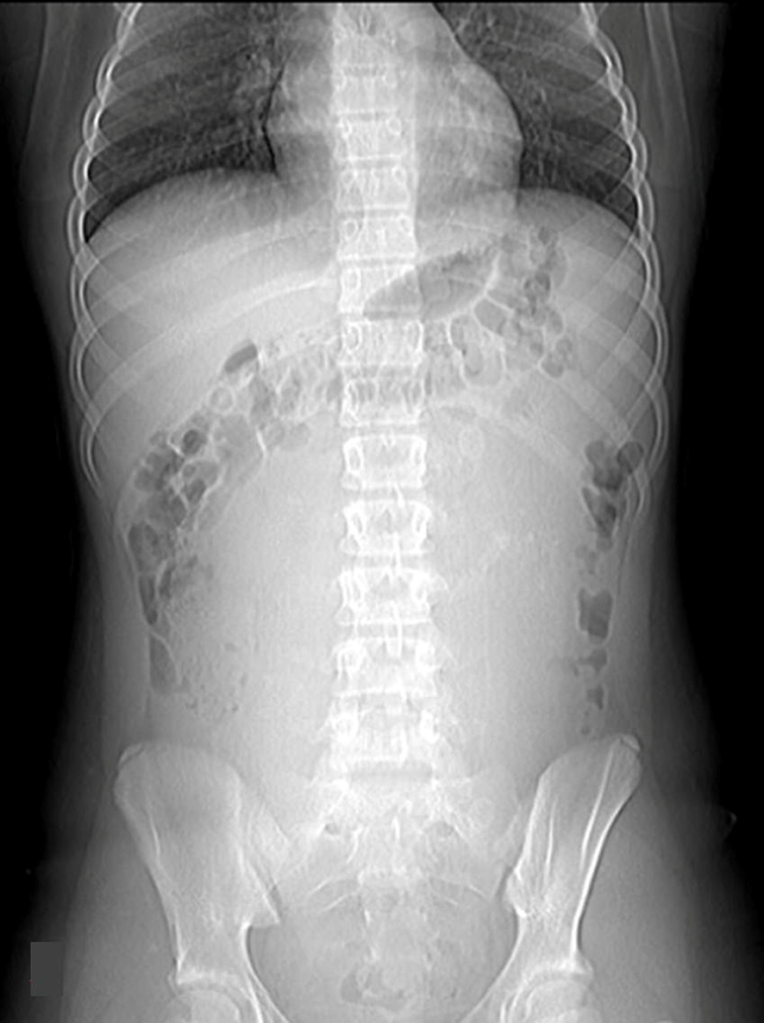

La radiografía simple de abdomen puede distinguir la dilatación de asas intestinales de delgado frente la dilatación del marco cólico, valorando la posible localización de la obstrucción

FECALOMA

El fecaloma es una acumulación de heces en el recto o en el colon, que taponan el flujo normal del tracto intestinal, la localización más frecuente es en colon sigmoideo y recto. Puede presentarse como episodio de dolor abdominal, vómitos por obstrucción e incluso diarrea por rebosamiento. También es preciso la realización de diagnóstico diferencial con masas en hipogastrio. Las opciones de tratamiento son los enemas, laxantes, evacuación rectal para aliviar la impactación fecal, e incluso cirugía si los métodos conservadores fallan.